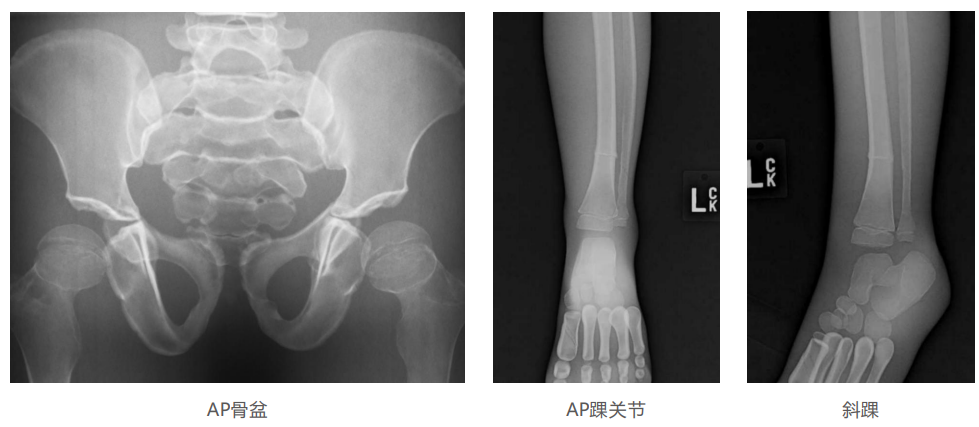

模體的大小和結構都代表了人體模體,使其便攜和易于定位。包括頭、胳膊和腿在內的整個身體。該系列包括六個部分的模體可單獨或作為一個完整的集合。

右肢有伸直或彎曲兩種配置。左臂和左腿可選伴有或不伴有內嵌骨折。

骨折版本包含最常見的人體骨折類型 ,包括脛骨扣帶骨折和腓骨普通骨折;

第一跖骨骨折;橈骨切開復位骨折 ,第二中間趾骨常見骨折。組件由適當的聚氨酯和環氧材料制成,模擬人體組織的X射線衰減特性,用于診斷和治療能量范圍(50 keV - 25 MeV) 。 材料經久耐用 ,耐沖擊,適合連續搬運。透明的軟組織有助于解剖標志的視覺指示。